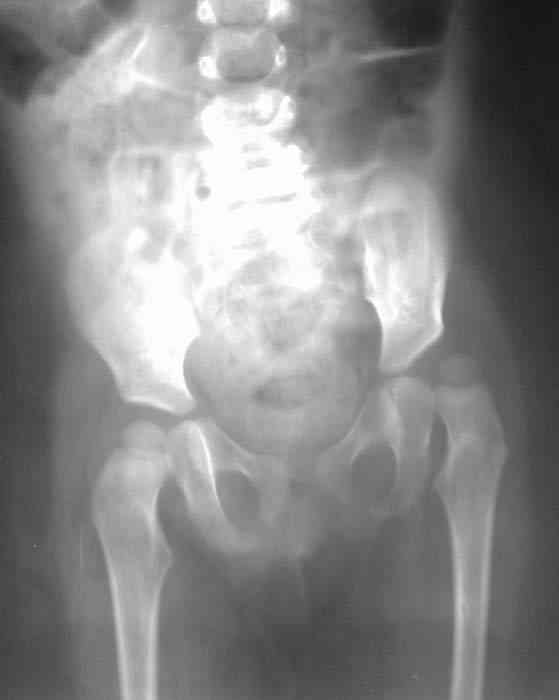

Уважаемые коллеги!Окажите, пожалуйста, консультативную помощь! Девочка, 1 г 9 мДЗ: врожденная патология головного мозга, врожденная дисплазия, подвывих, приводящая контрактура левого тазобедренного сустава, микроцефалия, миоклонические припадки, грубая задержка психофизического развития, с-м Айкарди?

Жалобы родителей на укорочение левой ноги, невозможность ходить, сидеть. Впервые обратили внимание на укорочение левой нижней конечности 4 месяца назад. Осмотрена по месту жительства в ЦРБ, направлена в ДНИИТО. Ребенок от I беременности, I срочных родов, протекавших с анемией, осложненные преждевременным отхождением вод, вес при рождении 4100. В анамнезе - пупочная грыжа, респираторные заболевания, рахит, тетрапарез, судорожный синдром, сальмонельоз.

Особенности объективного осмотра в настоящее время:Умеренный тетрапарез. Признаки рахита (деформация костей черепа, четки). Дыхание пуэрильное. Тоны сердца ритмичные, шумов нет. Живот мягкий, безболезненный, печень +1,5 см. Склонность к запорам. Местный статус: резкое приведение левого бедра, относительное укорочение левой нижней конечности. Ограничение отведения в тазобедренных суставах, особенно слева. Гипертонус мышц левой нижней конечности. Ограничение сгибания в левом коленном суставе.

Объем движений (левый ТБС): сгибание-разгибание (фиксированное) 65-165; разведение - D 45, S 65. Положение сустава по отношению к линии Розера-Нелатона - D 0,5 см, S 1,5 см. Хронаксиметрия - возбудимость нервных стволов нижних конечностей в норме, двигательная реакция мышц типичная.

Hi, this is pretty typical windblown hip deformity: abduction on rt side, adduction on the lt(according to your anamnesis kind of CP. Lt side already subluxated , no treatment will lead to further dislocation.I think that best way for treatmen now is : adductor tenotomy on the lt + spica cast ( 50-60 degrees abduction with wood bar between legs), after 6 weeks change to another 6 weeks; than for 6 months night plastic abduction brace.